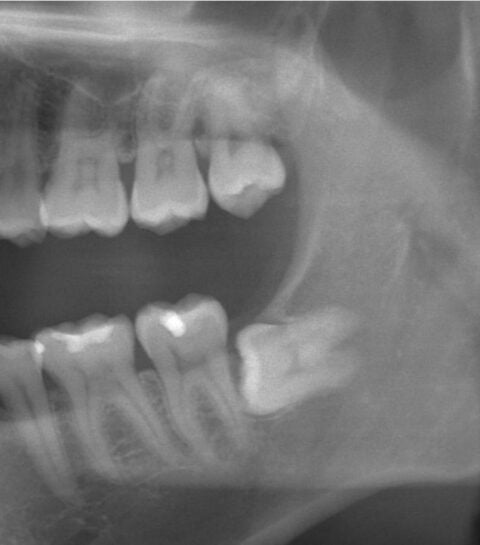

■親知らずが横向きに生えていたり、根っこの部分が神経に近い等、当院で安全に抜歯を行うことが可能でございます。

(※必要に応じて、当院に完備しておりますCT撮影をする場合もございます。)

■他院でお断りされた横向きの親知らずの抜歯も当院では無痛リラクゼーション治療で寝ている間にお痛みや音を感じることなく施術することが出来ます。(※ごく稀に神経に癒着しているようなクリニックレベルで非常に困難な物のみ提携大学病院へ紹介する場合があります。)